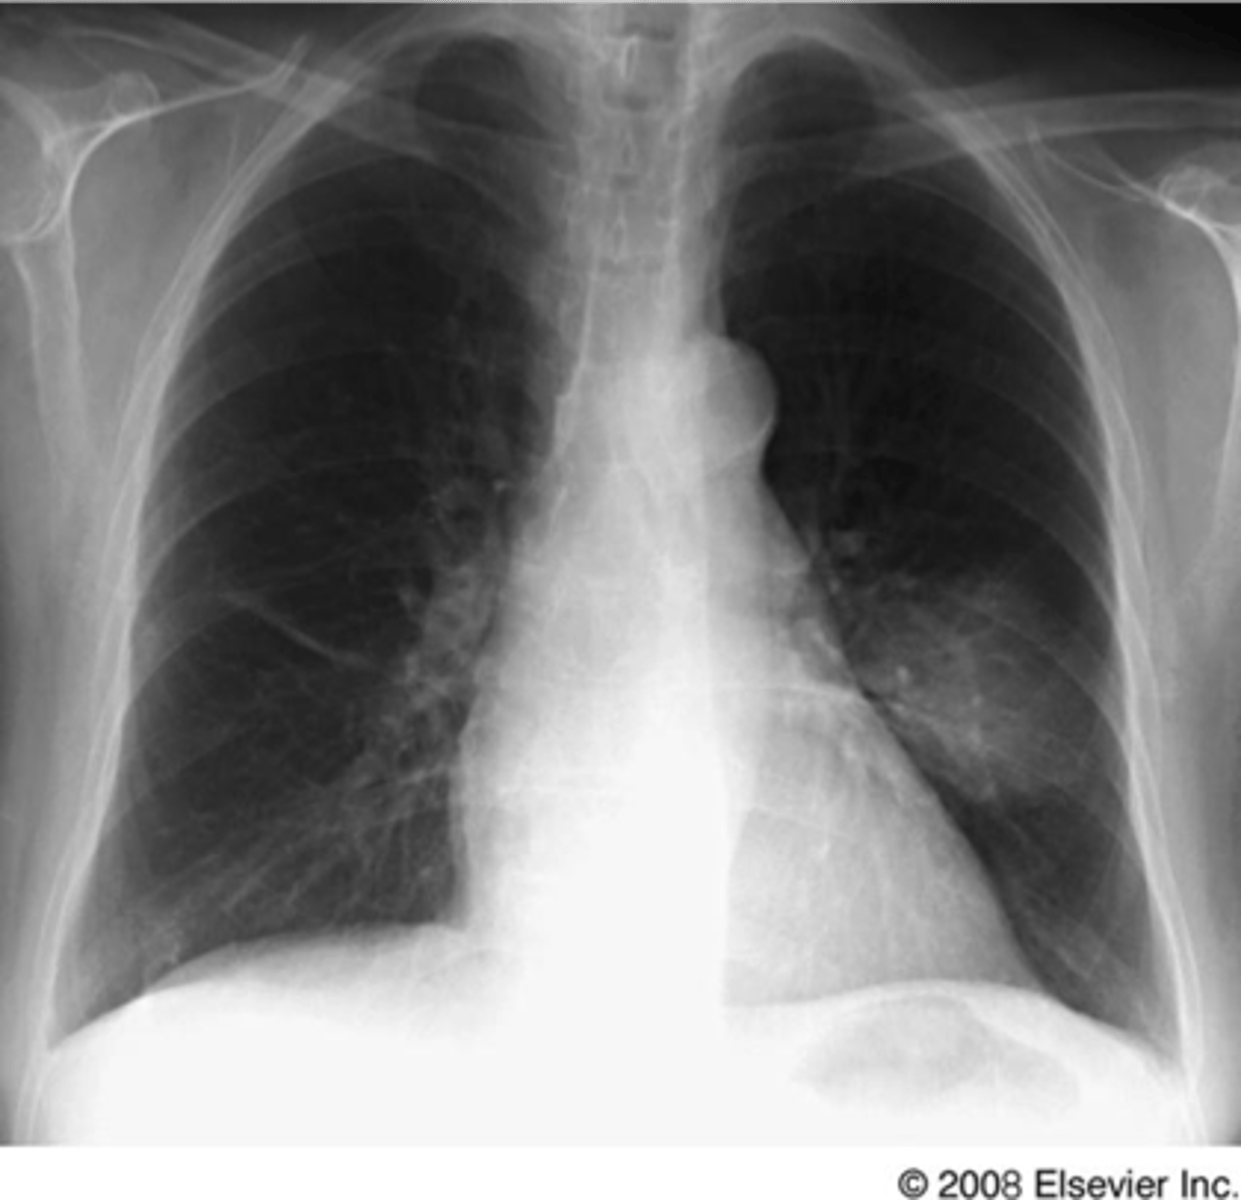

air bronchogram- alveolar consolidation LUL